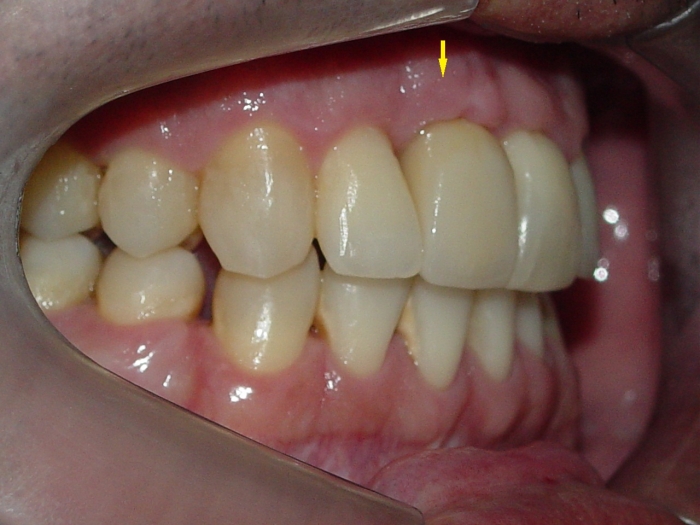

Imagem inicial